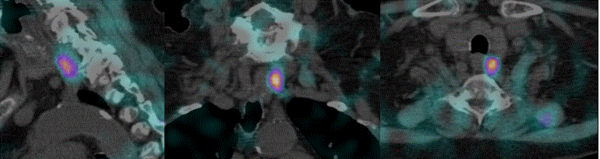

Si, dans le cancer du sein, l’imagerie planaire est souvent suffisante pour déterminer de façon précise la localisation anatomique du ganglion sentinelle, la situation peut être plus délicate dans les cas de mélanomes où le site de drainage lymphatique n’est pas toujours évident et les régions anatomiques complexes. Le SPECT/CT permet alors d’augmenter la précision anatomique en indiquant la profondeur et la localisation précise du ganglion sentinelle.  La connaissance pré-opératoire précise de la localisation anatomique permet de faciliter le geste chirurgical consistant à extraire le ganglion sentinelle pour analyse et de planifier la voie d’abord (fig. 5).

Figure 5 - Cancer du sein : ganglion sentinelle localisé par SPECT/CT